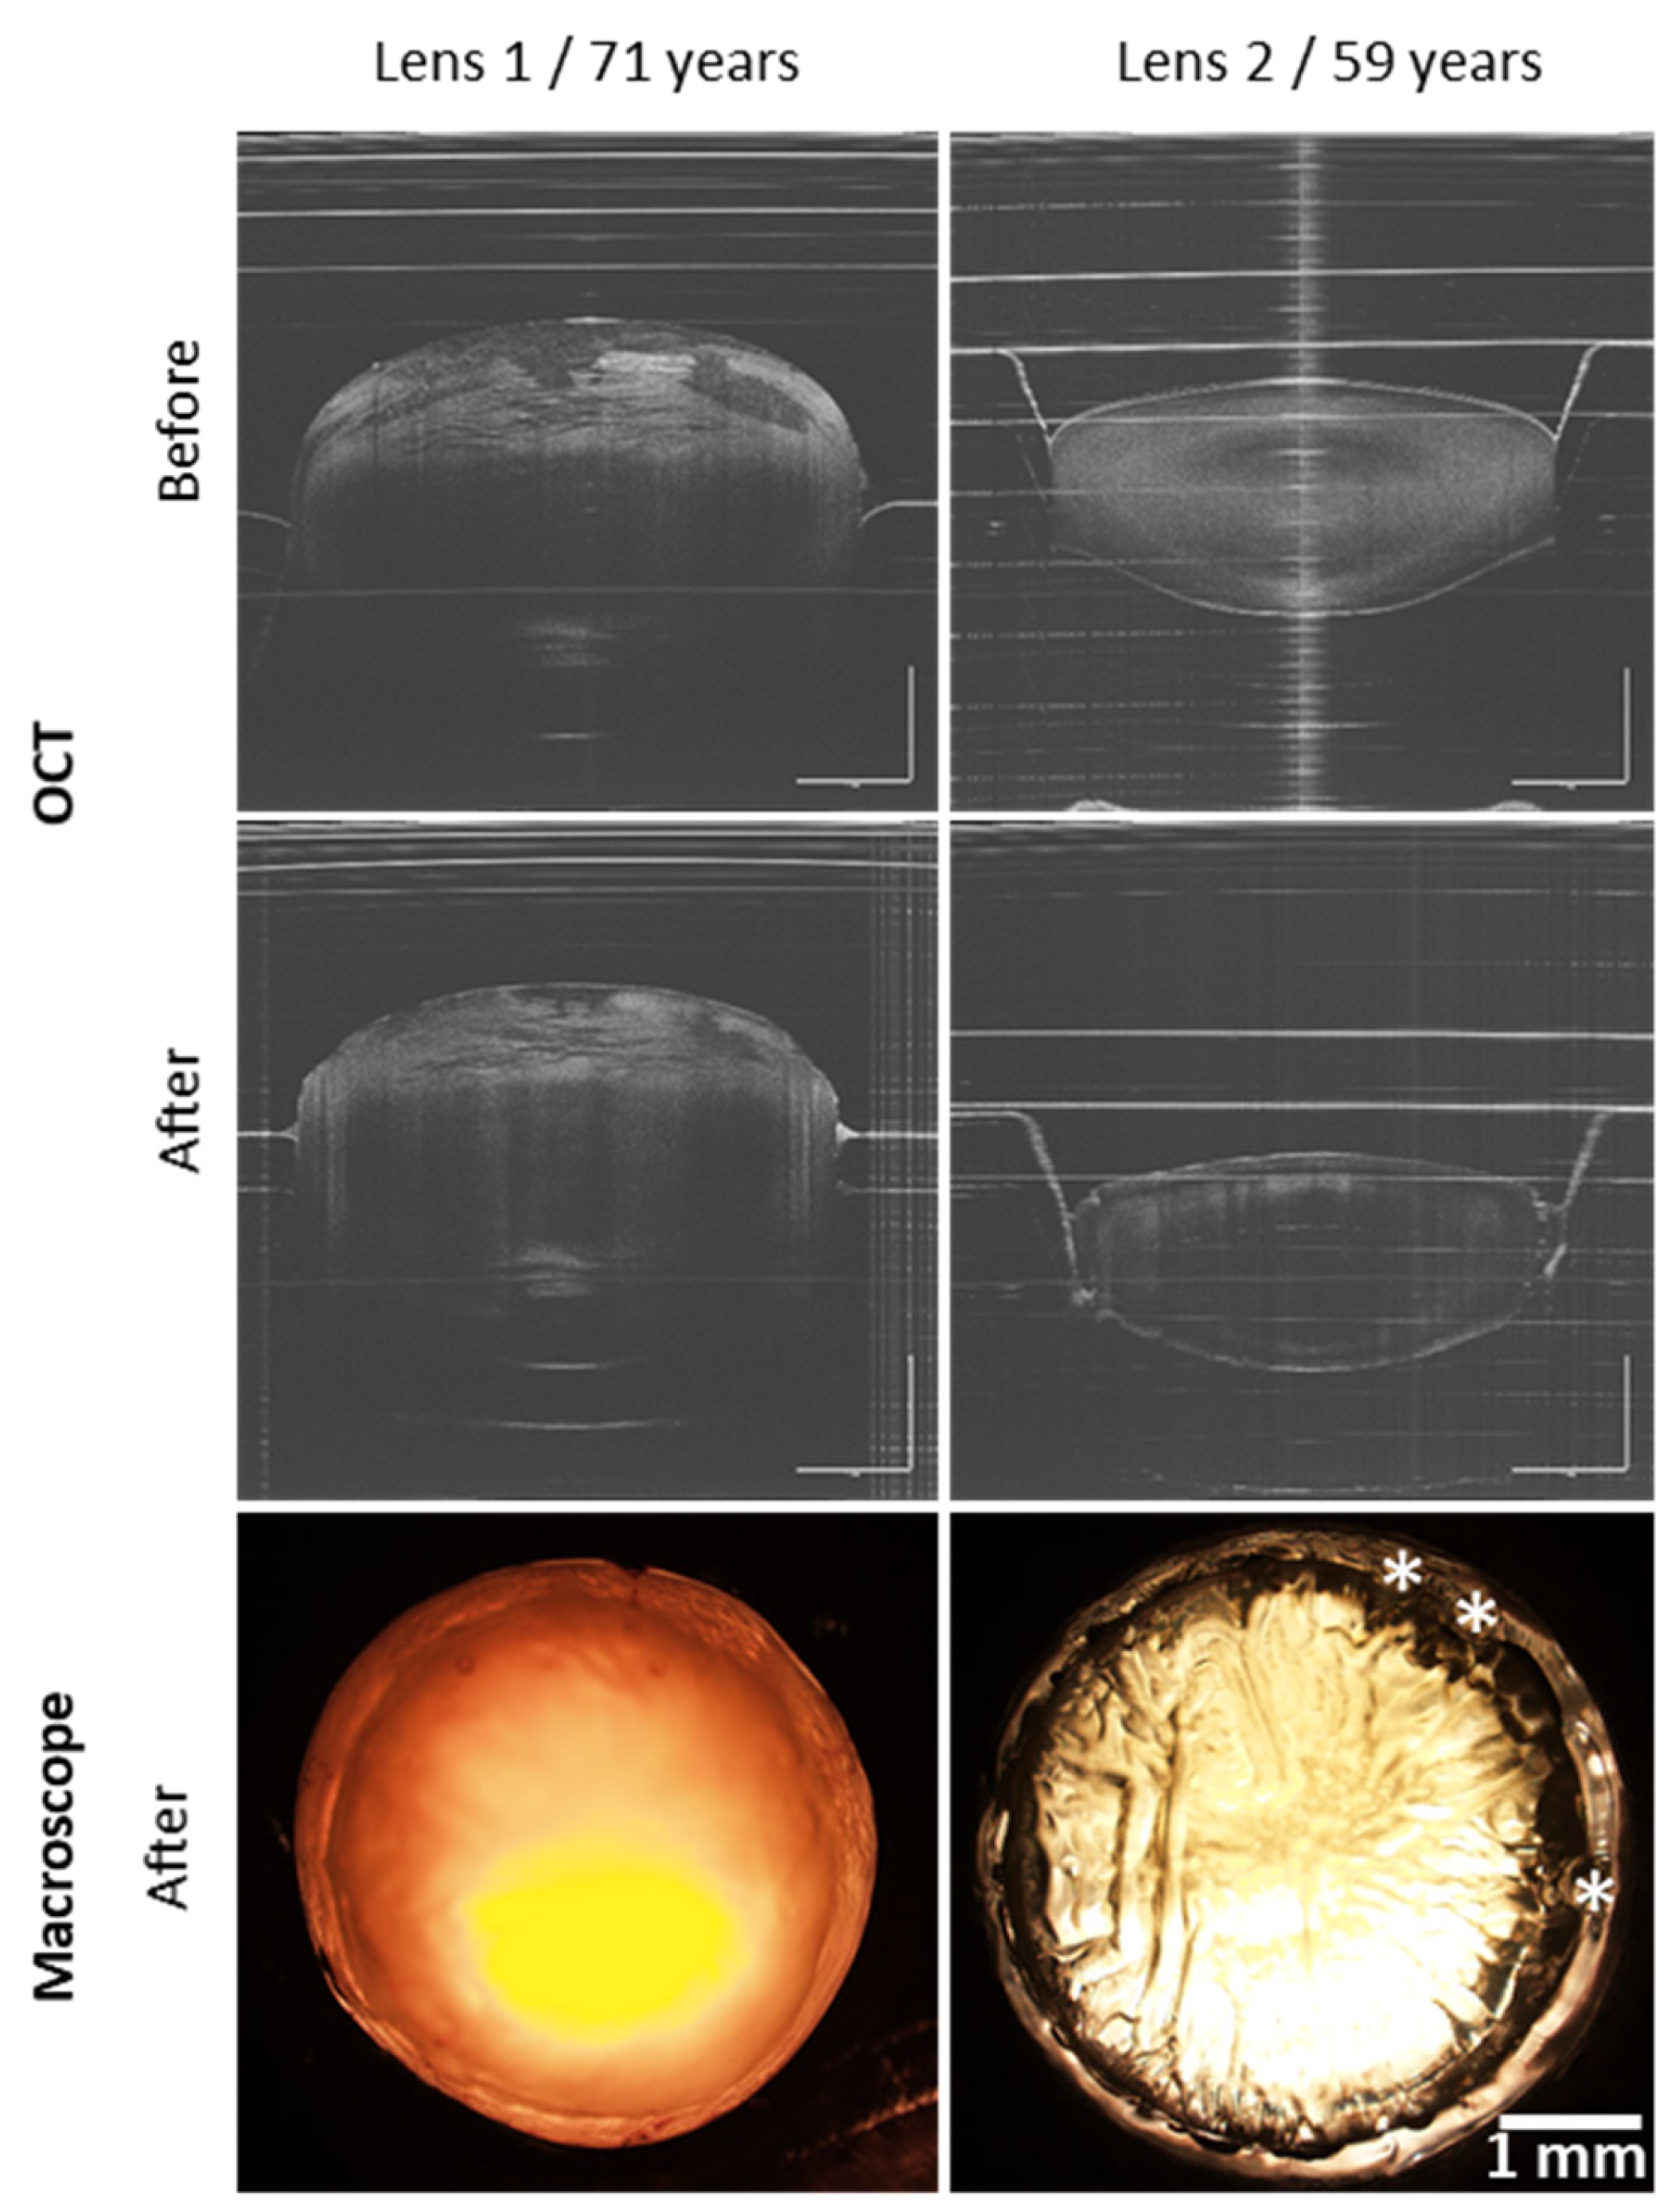

3.1. Femtosecond Laser Cutting of Lens Capsule Discs